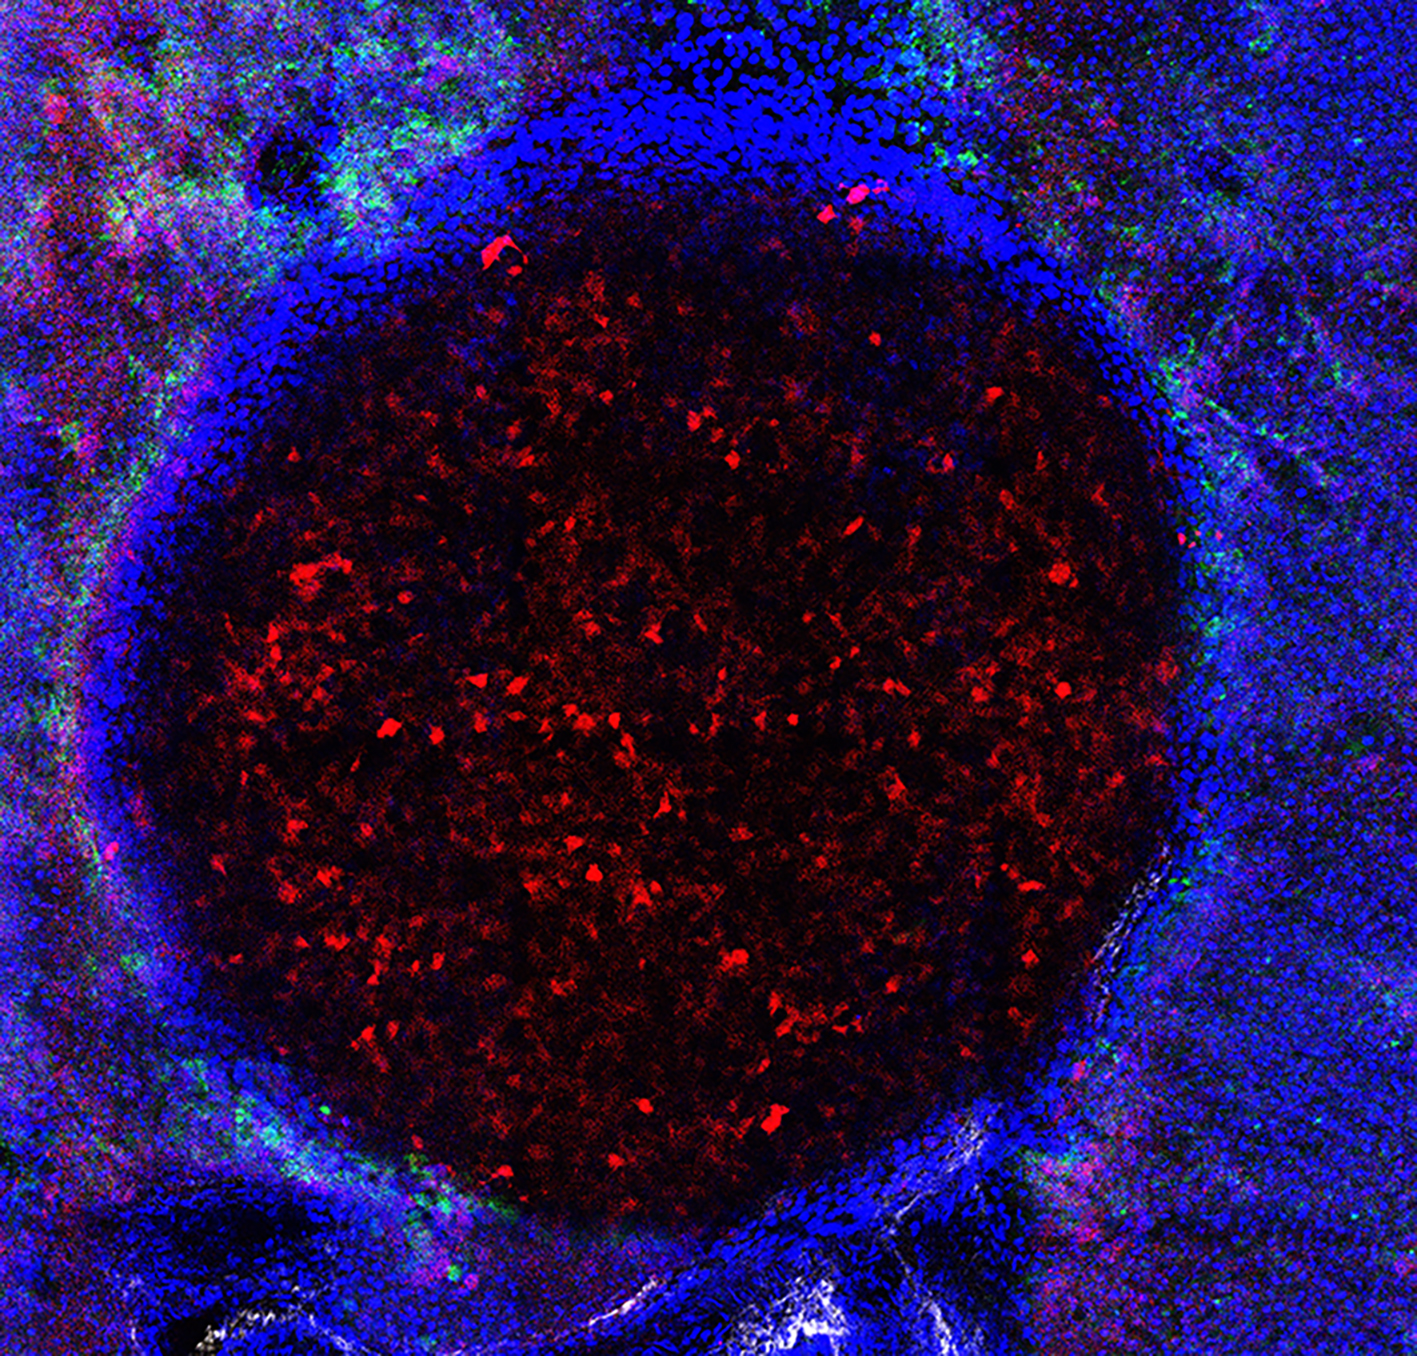

Tilescan human HCC – this shows human HCC cells (red) engrafted “entering” a human PCLS, nuclei (blue), with added immune cells (green). The orthoganol projection  of sections from the top to the bottom of the slice (250 microns total) shows that the cancer cells penetrate throughout the slice, the immune cells labelled green, surround the tumour.

The image above shows human HCC cells (red) engrafted “entering” a human PCLS, nuclei (blue), with added immune cells (green). The orthogonal projection  of sections from the top to the bottom of the slice (250 microns total) shows that the cancer cells penetrate throughout the slice, the immune cells labelled green, surround the tumour.